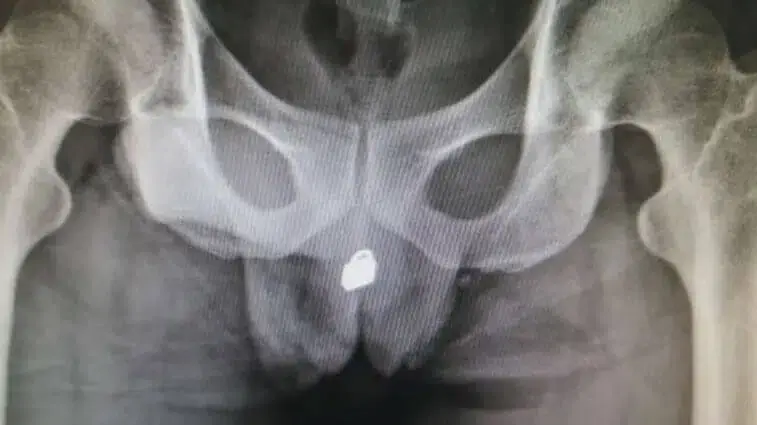

Aos médicos, o homem (que não quis ser identificado) recusou revelar o que se passava mas, depois de fazer um raio-X, o problema ficou à vista. Acabou por revelar que tinha inserido o pequeno objecto metálico na uretra e que depois o empurrou para dentro do pénis para ter prazer sexual.

O cadeado de pequenas dimensões acabou por entrar na bexiga e causar um bloqueio e muitas dores ao homem. Foram feitos vários testes até se decidir se era ou não seguro operar o paciente e a cirurgia implicou extremo cuidado.

Os médicos acabaram por conseguir retirar o cadeado depois de fazerem uma incisão na bexiga. O homem continua internado e deverá ficar com sequelas permanentes no aparelho urinário.